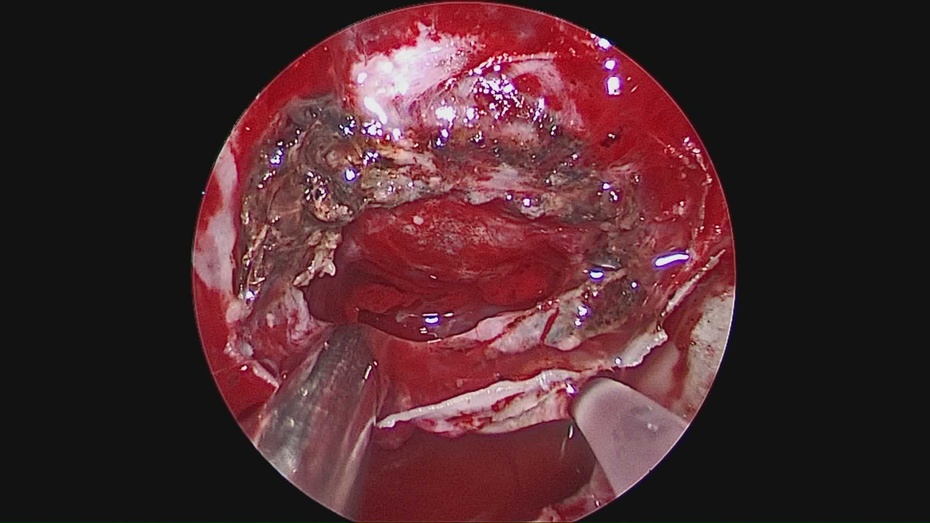

神经内镜辅助手术治疗垂体瘤卒中一例

图片尺寸792x656